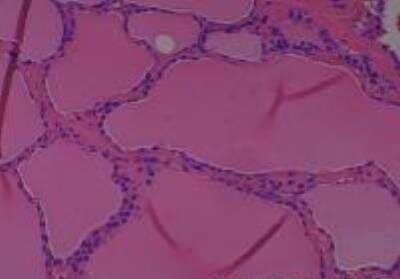

Scientific Data Images for Human Multi Tissue MicroArray (Normal Adjacent)

Hematoxylin & Eosin Stain: Human Common Tissue MicroArray (Normal Adjacent) [NBP2-30215] - 01. Stomach